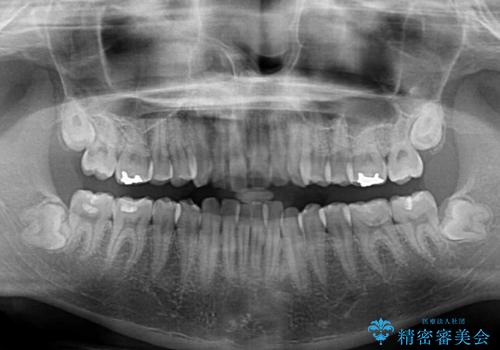

- 上下前歯のデコボコを気にして来院された患者様です。

前歯のデコボコ以外に左側の奥歯の咬み合わせに問題がありましたが、価格を抑え、短期間で気になる前歯を治したいとのことでした。

こちらの患者様は、事前のシミュレーションにより、インビザライン・ライトでは前歯のデコボコを解消しきれないことが分かったため、通常のインビザライン(コンプリヘンシブパッケージ)での治療が必要となりました。

しかし、費用面や期間で悩んでいらっしゃったため、左側臼歯の問題は解決せずに前歯のデコボコのみを改善するシミュレーションを作成し、治療を行うこととしました。

写真より左側臼歯の咬合がタイトではないことが分かりますが、こちらは保定期間に徐々に咬合させていくこととしました。